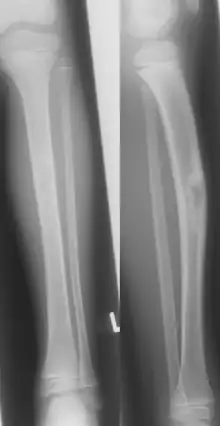

| Jaffe-Campanacci-Syndrome, boy 7 Y, tibial bowing and cortical/subcortial mixed sclerosis | |